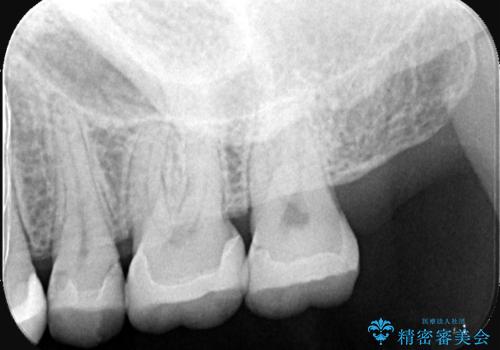

- 主訴:詰め物が欠けてしまった。

歯冠色インレーが一部欠けてしまい、他院にて部分的に樹脂のコーティング剤を付けてもらっている状態でした。

欠けている大きさが大きかったため、やり替えを提案しセラミックインレーでのやり替えとなりました。

他院にてセットしたセラミックインレーの一部が研磨では対応できない程大きく欠けてしまっていたため、やり替えとなりました。再度欠けぬよう、歯質を削り厚みを確保しています。